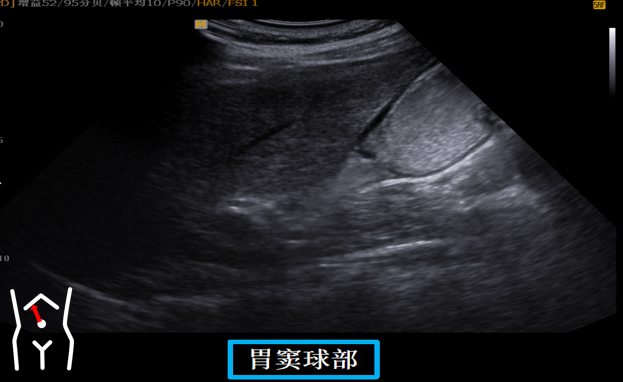

患者从右卧位改成平卧此时头也随着患者改变体位而由横切改为纵切在脐孔与右肋缘连线处扫出胃窦幽门管幽门孔球部降部水平部